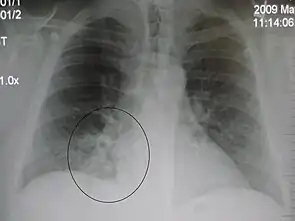

AP CXR showing left lower lobe pneumonia associated with a small left sided pleural effusion

AP CXR showing right lower lobe pneumonia

AP CXR showing pneumonia of the lingula of the left lung

Right upper lobe pneumonia as marked by the circle.

Left upper lobe pneumonia with a small pleural effusion.

Right lower lobe pneumonia as seen on a lateral CXR